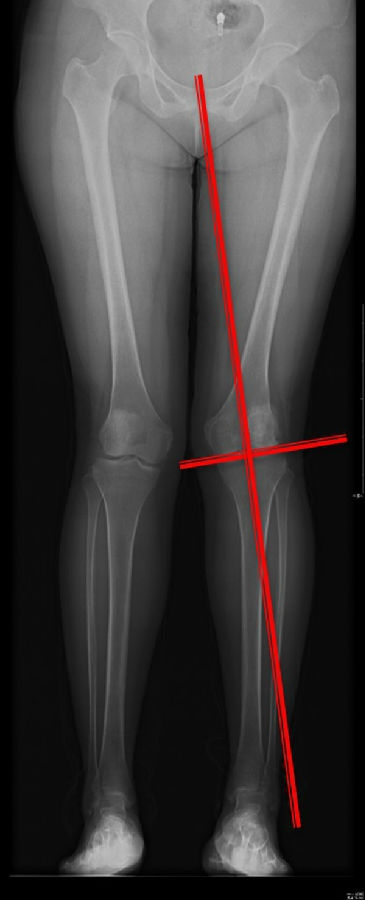

患者二,女性,膝外翻,膝外侧疼痛。通过做畸形分析后发现,该患者同时存在股骨侧畸形、胫骨侧畸形和关节内畸形(LDFA=82°,MPTA=104°,JLCA=6°)。

对于这类病人如何进行术前设计的关键点就在于目标力线应如何设计。要在骨性截骨的时候纠正骨性畸形,关节内畸形要通过关节内的方法解决。因为JLCA不平行,所以要同时画股骨侧关节线和胫骨侧关节线,并垂直于股骨侧关节线做出股骨侧目标力线,垂直于胫骨侧关节线做出胫骨侧目标力线。

根据各自目标力线,分别计算股骨内侧闭合和胫骨内侧闭合角度。

此患者股骨内侧闭合6°,经股内侧闭合13°。